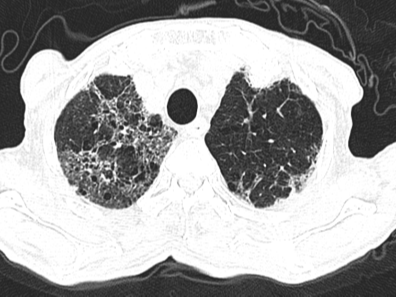

在接下来的救治过程中,挑战接踵而至。患者相继出现了血痰、血便、顽固性的低钠血症和心脏早搏等问题,治疗团队如同闯关一般,对每一个新情况都及时研判并调整用药策略。随着治疗的深入,患者的体温首先恢复正常,成为病情好转的曙光。之后的复查CT显示,肺部炎症开始逐步吸收。虽然过程中出现了肺纤维化的迹象,但通过加用抗纤维化药物尼达尼布,这一进程也得到了有效干预。